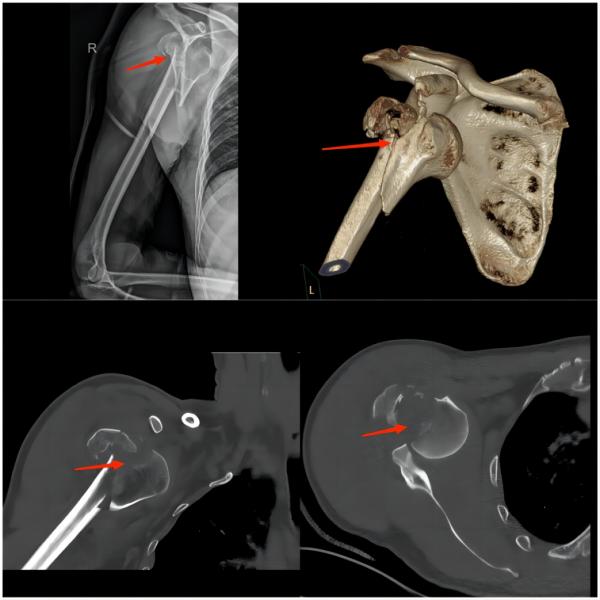

⑤肩部损伤

(上图为右肱骨粉碎性骨折伴肩关节脱位)

常见原因:比赛中球员大力射门,守门员奋力扑救,这种巨大外力易导致守门员肩部损伤,如肩关节脱位及骨折。